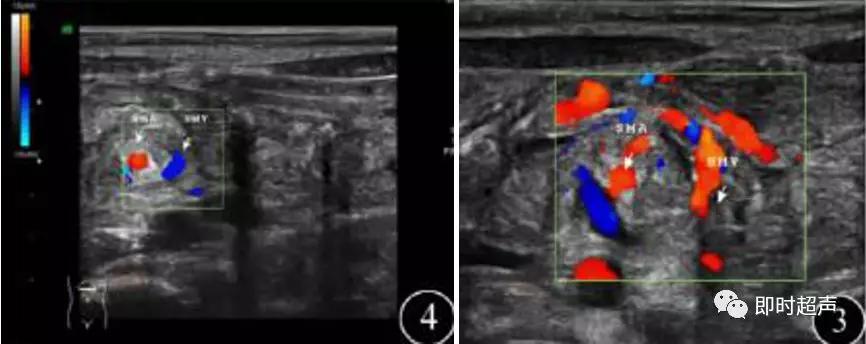

肠系 膜 上 血 管 根 部 呈 现SMV/SMA位 置 逆 转, 即SMV位于SMA左侧

第二步 (两步扫查法):重点进行肠系膜血管走行的扫查。在第一步的基础上探头顺时针旋转180°、配合患儿呼吸适度加压,并实时左右侧动探头,必要时做轻微的角度调整,清晰显示SMA和SMV主干血管直至纤细的末端 ,同时尽可能显示其主要分支,观察其走行情况。

SMV根部起始直至纤细的末端,“V”为SMV

SMA自AO发出直至纤细的末端,“A”为SMA

SMV连同所属的肠系膜和肠管围绕SMA发生顺时针旋转,超声横切面下呈现类似风暴引起的 “漩涡”征象

肠系膜动静脉位置异常,彩色血流漩涡征

- SMV/SMA位置逆转:SMV位 于SMA左 侧。

- Whirlpool征:SMV围绕SMA形成漩涡征象